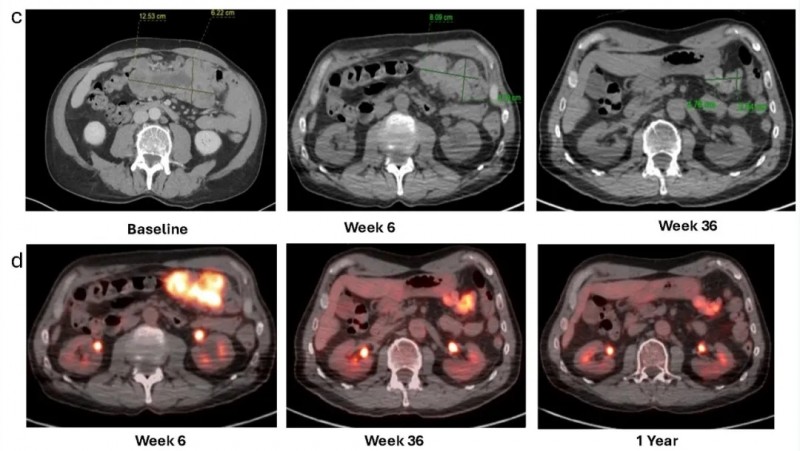

结果显示:根据实体瘤疗效评价标准(RECIST)v1.1,治疗6周后患者影像学表现达部分缓解(PR)。12个月随访时缓解持续,靶病灶缩小65%。PET/CT显示,治疗后6周~1年,代谢活性持续下降(详见下图c、d)。

▲图源“Front Immunol”,版权归原作者所有,如无意中侵犯了知识产权,请联系我们删除